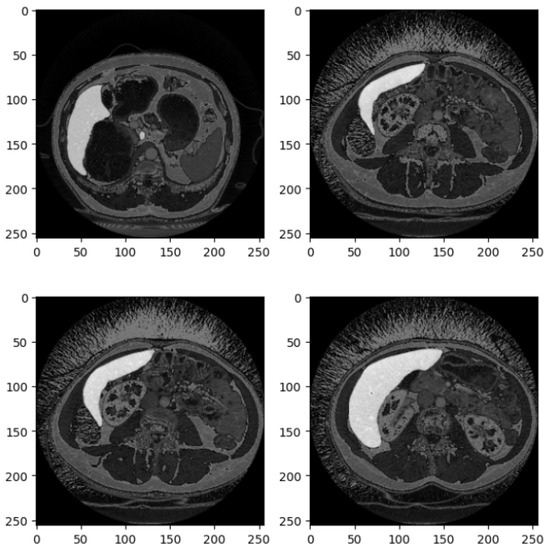

Figure 2 shows four examples of CT liver images related to the DI dataset.

Figure 2 presents four axial slices from a CT scan, likely of the abdomen. The scans are in grayscale, adhering to standard medical imaging practices. Each image slice is square with dimensions of 250 × 250 pixels, potentially corresponding to a specific magnification level or scale within the imaging modality. These slices represent axial (cross-sectional) views of the abdomen, showcasing various abdominal organs, including the liver, kidneys, stomach, intestines, and possibly sections of the spine and abdominal musculature.

In the top left image, sections of the liver (on the left side) and the kidney (on the right side) are visible, with part of the spinal column centrally located. The top right image depicts a slightly lower section of the abdomen, where the liver occupies a larger portion of the view, and a section of the bowel is observable. The bottom left slice reveals a broader section of the abdominal cavity, with distinct bowel loops that may show gas-filled intestines or contrast material. The bottom right image features the liver more prominently, extending across the section, and includes parts of the gastrointestinal system, possibly the colon.

The images appear to be contrast-enhanced, as indicated by the bright white regions representing areas of high contrast uptake, such as blood vessels or perfused organs. The overall quality of the images is high, with minimal noise, suggesting that they were acquired at an adequate resolution suitable for diagnostic or research purposes. The grayscale intensity is consistent across all slices, indicating uniform windowing and leveling, which is essential for evaluating the radiodensity of the tissues depicted.